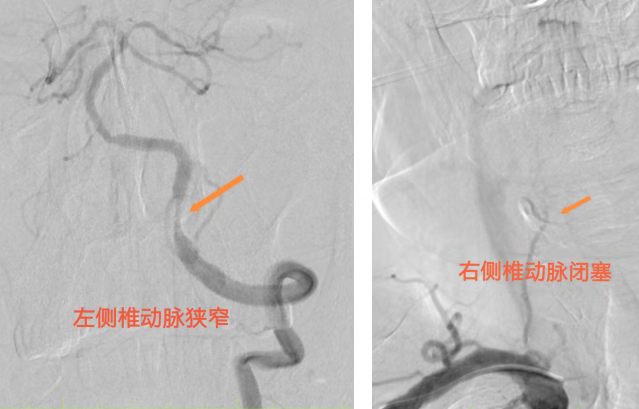

面对危急情况,我院立即启动急救绿色通道。经检测,患者碳氧血红蛋白浓度显著升高,急性一氧化碳中毒诊断明确。然而,病情远非如此简单:随后的影像学检查提示患者双侧小脑发生急性脑梗塞;通过脑血管造影(DSA)进一步探查发现,其右侧椎动脉已完全闭塞,而作为大脑后循环唯一供血来源的左侧椎动脉也存在重度狭窄。

这意味着维系患者呼吸循环中枢的“生命线”岌岌可危。长春国文医院神经介入团队迅速研判,决定在积极纠正缺氧、保护脑细胞的同时,立即进行介入手术干预以开通血管。术中,团队凭借娴熟的技术,将微导丝精准通过狭窄段,成功为患者左侧椎动脉实施了球囊扩张成形术及支架植入术。术后即刻造影显示,血管狭窄解除,血流恢复通畅。